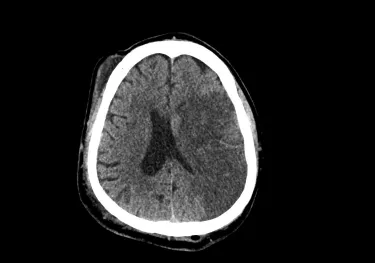

There are two types of strokes: ischemic, which occur when a blood vessel in the brain is blocked, and hemorrhagic, which occur when there is bleeding in the brain. In the case of an ischemic stroke, blockage of a blood vessel cuts off blood supply from a part of the brain. As brain cells lose oxygen, they die. Once they’re dead, they can’t be brought back to life. |

However, after a stroke, some cells on the perimeter of the initial stroke injury may still be salvageable. Physicians refer to this injured but salvageable tissue as the penumbra.

“There’s a lot more opportunity to use our knowledge and expertise, like brain scans, for example, to get a sense for what types of therapies will really help one specific person,” Leung said.

Leung used the example of a person who has lost their ability to speak due to a very severe stroke on the left side of their brain. Standard speech therapy may not work very well for them, since much of their language-processing brain tissue has been damaged. The knowledge of where the stroke occurred, gained via brain scans, might indicate that music therapy—which harnesses the abilities of the right side of the brain—could work very well for them.